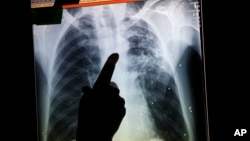

Sebuah studi baru menemukan bukti bahwa bakteria penyebab TB tetap hidup meski sudah diobati. Beberapa bulan setelah dirawat karena TB paru-paru dengan antibiotik yang banyak, 99 orang yang negatif HIV di Cape Town, Afrika Selatan, dipindai paru-parunya.

Para peneliti pada Universitas Stellenbosch menggunakan CT-scan, jenis X-ray yang lebih rinci, dan PET-scan, yang bersinar untuk mengungkap adanya kelainan paru-paru. Pemindaian pada 76 pasien, yang diduga sudah sembuh, menunjukkan masih adanya peradangan paru-paru dan jaringan abnormal seperti pada pasien yang belum diobati.

Setahun setelah pengobatan, 50 pasien menunjukkan keadaan paru-paru serupa, meskipun sebagian besar jaringan abnormal atau lesi telah mengecil ukurannya. 16 pasien lainnya bebas dari lesi.

Para periset juga mendeteksi kandungan genetika pada air liur dan lendir dari 34 pasien, indikasi bahwa bakteri hidup masih berada dalam paru-paru mereka. Para periset itu terkejut.